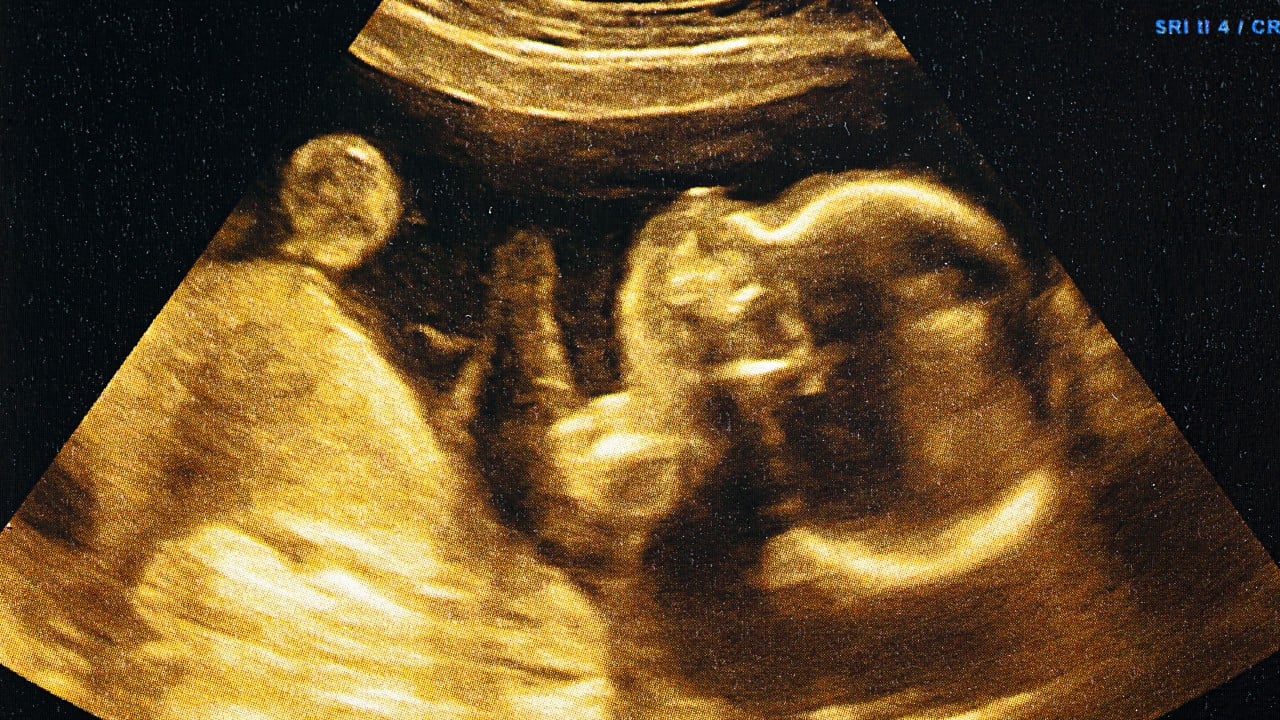

A China-led team has built the world’s first mini-womb on a chip that can fully replicate the “invasion” of human embryos in the uterus during early pregnancy. Their 3D model on a microfluidic chip can be used to uncover the mysteries behind human embryo implantation and lead to personalised treatments for women struggling to get pregnant. The team led by researchers from the Chinese Academy of Sciences Institute of Zoology said that while achieving a better understanding of human implantation was “crucial”, it was challenged by ethical constraints and limited…